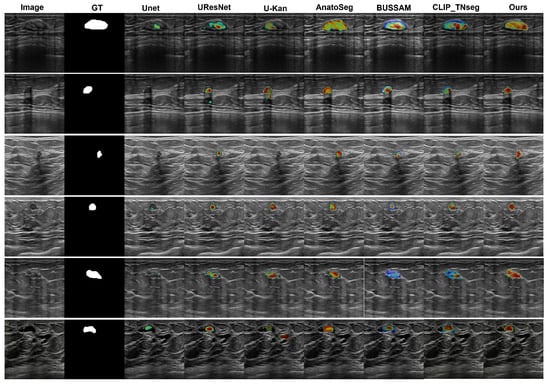

3.3. Qualitative Visualizations

We employed Grad-CAM overlays to visualize image regions that most influenced the predicted masks (Figure 4). Among the compared methods, U-Net [12], U-ResNet, U-KAN [53], and AnatoSegNet [54] are non-prompt methods; BUSSAM [43] and CLIP-TNseg [46] are prompt-guided; and XBusNet uses dual prompts (global and attribute-conditioned). Non-prompt baselines frequently display diffuse responses in low-contrast tissue, particularly posterior to the lesion, corresponding to missed or fragmented masks. Prompt-guided methods improve spatial correspondence; CLIP-TNseg may still exhibit scattered hotspots around speckle, whereas XBusNet shows concentrated activation adjacent to lesion boundaries and within the mass. For very small lesions, the salient regions for XBusNet overlap the recovered mask more consistently, in line with the small-lesion gains reported in Table 2. These visualizations are qualitative and are not treated as formal explanations.

Figure 4. Grad-CAM comparison. Colors map low→high attribution (blue→red), normalized to [0, 1] with a shared scale across images/models.